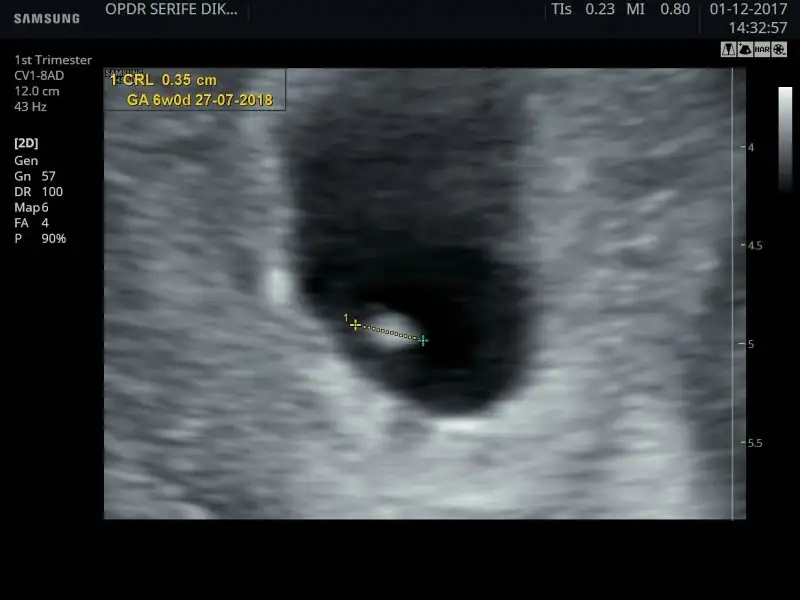

Eki Görüntüle 2075154 6 haftalık vajinal ultrason Ramzi teorisine göre kız sanırım ama vajinal olunca değişiyormuş